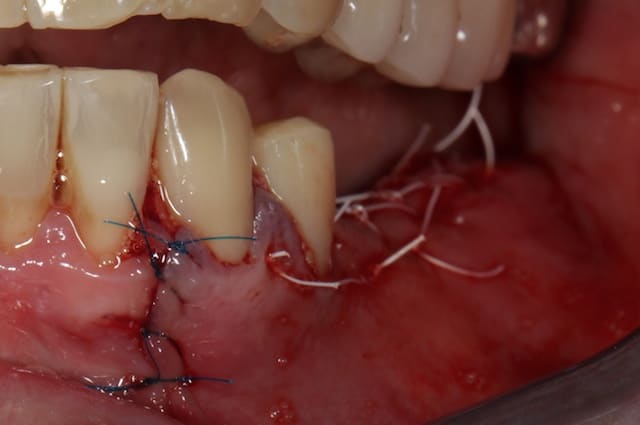

Puisqu'on parlait de ROG verticale, en voici une toute fraiche de ce matin, comblement osseux 50/50 os autogène et Bio-oss le toute recouvert par une membrane PTFE armé titane pinsé.

Juste un truc il me semble avoir lu que les nouvelles membranes cytoplast ptfe peuvent être exposées (brochure dental force adf).

Le fil de suture c'est aussi du ptfe?

Il semblerait que les membranes en PTFE dense ( comme les cytoplast ) soient moins sensibles aux infections une fois exposées que les membranes en PTF expansées ( gore tex qui n'existent plus) mais je ne pense pas que tu puisses laisser exposée pendant plusieurs mois ( 9 mois dans le cas de ROG verticale ) une membrane exposée.

Le fil aussi est en PTFE.